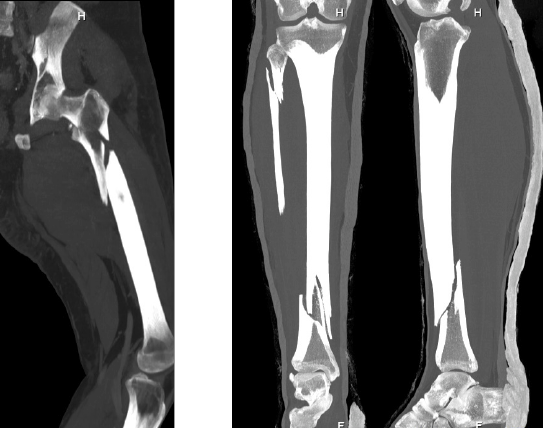

FRACTURA DE FEMUR Y TIBIA

Son roturas en los huesos largos de la pierna. La mayoría necesitan cirugía para volver a unir los huesos y recuperar la función normal de la pierna.